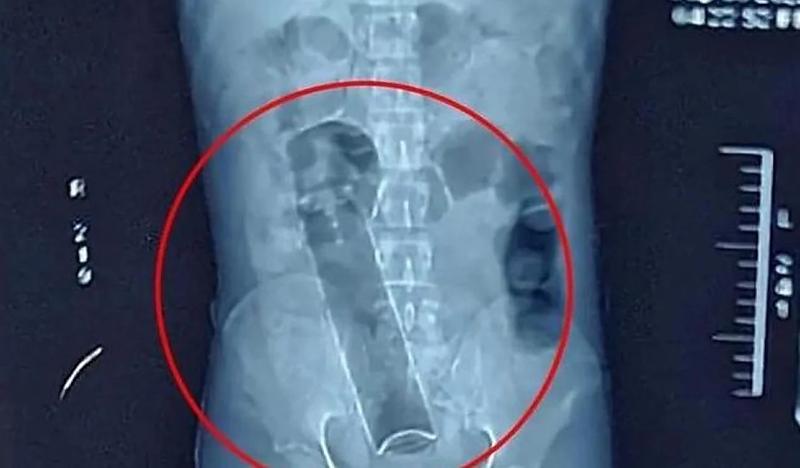

Segundo informações repassadas, o homem enfrentou um incidente com um frasco de desodorante, que acabou ficando preso em seu corpo. Assustado e sem conseguir remover o objeto sozinho, ele decidiu buscar ajuda profissional.

A equipe médica rapidamente realizou o procedimento necessário para a remoção do objeto, com total sucesso e sem complicações. Após ser avaliado e permanecer em observação por algumas horas, o paciente recebeu alta hospitalar.